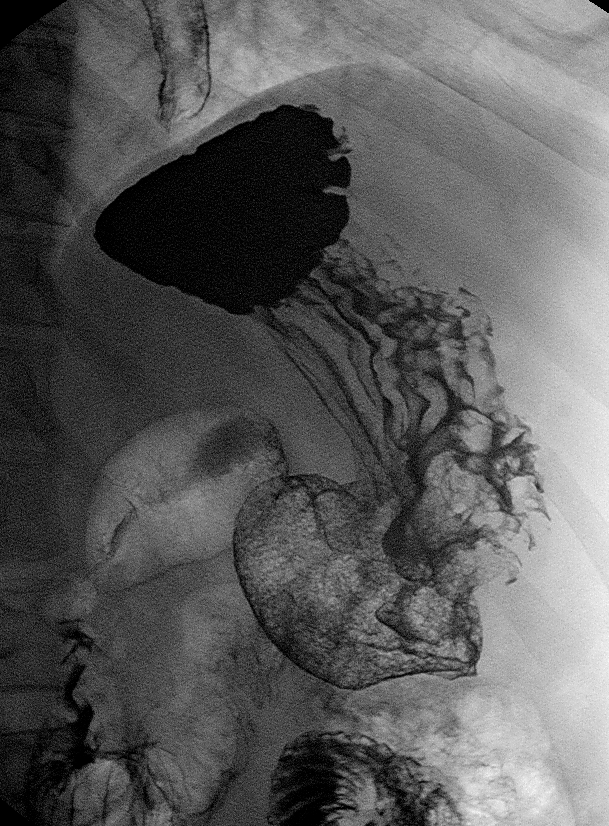

06.06.2011 Рентгеноскопия желудка и КТ-органов брюшной полости.

Пациент 52 года, жалобы на боли в эпигастрии.

Рак большой кривизны с мтс печени?

Представленный случай конечно уже запущенный, аденокарцинома по большой кривизне желудка с множественным метастазирвоанием паренхимы печени, кстати на КТ четко видно утолщенную инфильтрированную стенку желудка.